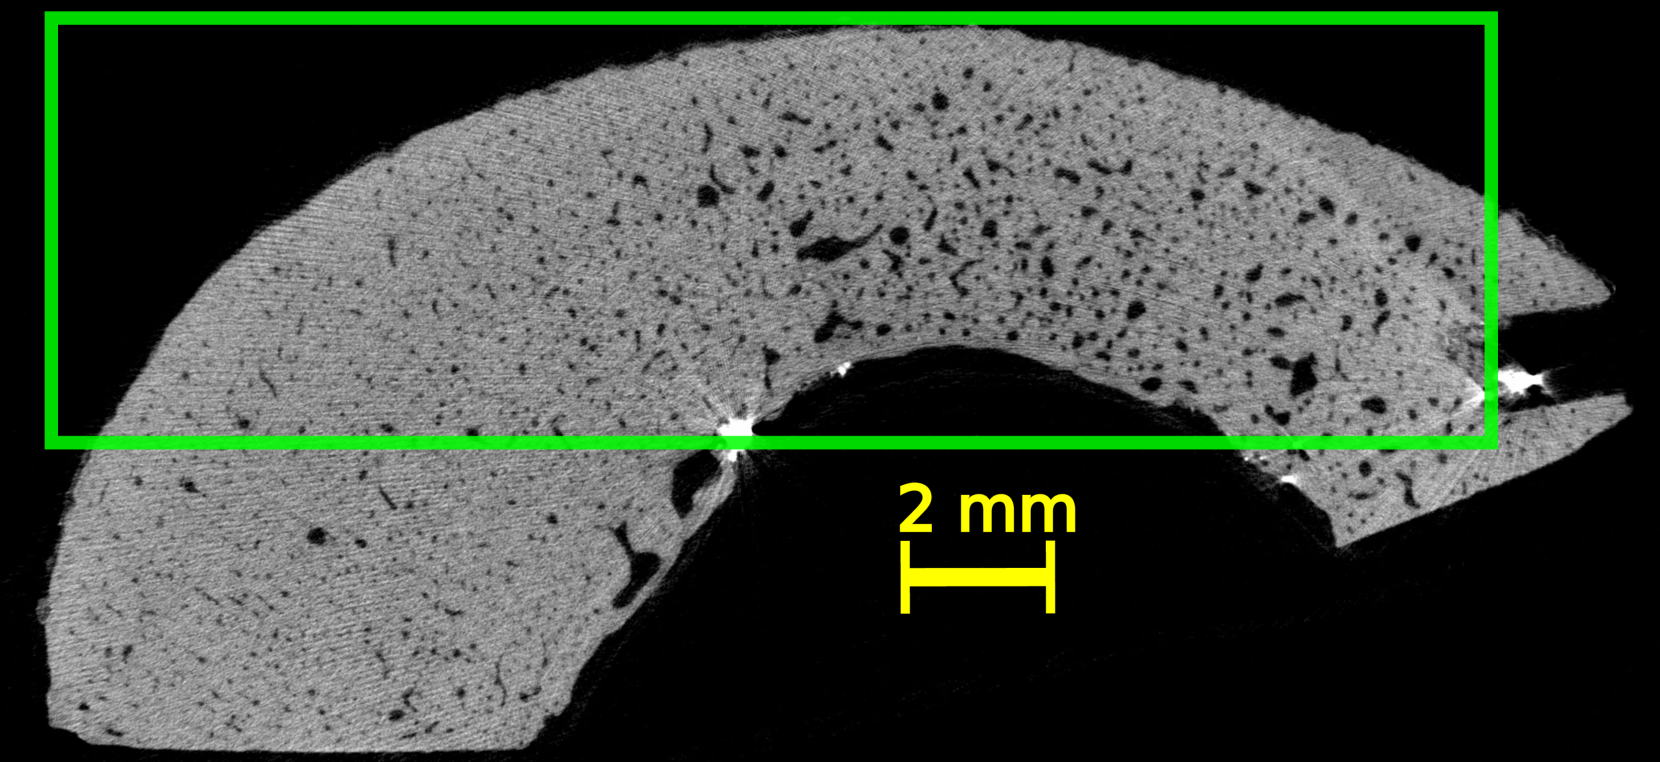

Four volumes of interest (VOI) were defined within the three-dimensional (3D) HR-µCT image of each sample. The thickness (direction of the bone axis) and width of the VOIs were 15 and 20 mm, respectively. The height of the VOIs varied between 8 and 10 mm, depending on the cortical thickness and diameter of each sample. Figure LABEL:method:example_xray_slice shows a two-dimensional (2D) slice in the transverse plane extracted from each VOI for all the samples. The VOI’s dimensions approximately correspond to the thickness (probe elevation direction), lateral dimension (probe aperture) and depth of the US image.

The initial step was to apply a Gaussian filter (round kernel of radius 2 or 3, depending on the sample) to remove acquisition noise. Then, the VOI were binarized using 3D Otsu method [31]. Given that this study focuses on the cortical bone tissue, we removed, in the endosteal region, the bone remnants resulting from a trabecularization [5] of the cortex (samples 4 and 5, see Figure LABEL:method:example_xray_slice and Figure S1 in supplementary materials). To do this, we used kernel filtering (either Kuwahara or Uniform kernels with a radius of 2) and morphological operations to close all pores below a specific threshold diameters, thereby generating a mask that excluded trabecular regions. The specific choice of kernel and parameters varied across samples to accommodate the high morphological variability among the samples (Figure LABEL:method:example_xray_slice).

The 20 VOIs (4 VOIs in each of the 5 samples) showed a great diversity in terms of cortical thickness, porosity, and distribution of pores (Figure LABEL:method:example_xray_slice). Cortical thickness estimated from micro-CT images ranged from 2.5 to 6.3 mm (Table LABEL:table_chap_4:pore_stat_samples_combined). The microstructure parameters are summarized in Table LABEL:table_chap_4:pore_stat_samples_combined. Samples 1 and 2 had the lowest porosity (5–6.4 % and 5.3–6.7 %, respectively) and no large pores (Lg.Po.Dm 175 m). Sample 3 showed moderate porosity (7–12.3 %) with moderately large pores (Lg.Po.Dm in the range 224–228 m). Samples 4 and 5 presented the highest porosity (12.2–16 % and 16.4–16.6 %, respectively) with 10% of the pores with diameter above 300 m. Sample 4 displayed the largest pores (Lg.Po.Dm in the ranged 334–423 m), which can be clearly seen in Figure LABEL:method:example_xray_slice. Porosity values and the porosity gradient from the periosteal to the endosteal surface seen in some samples are consistent with the literature data for elderly donors [27].